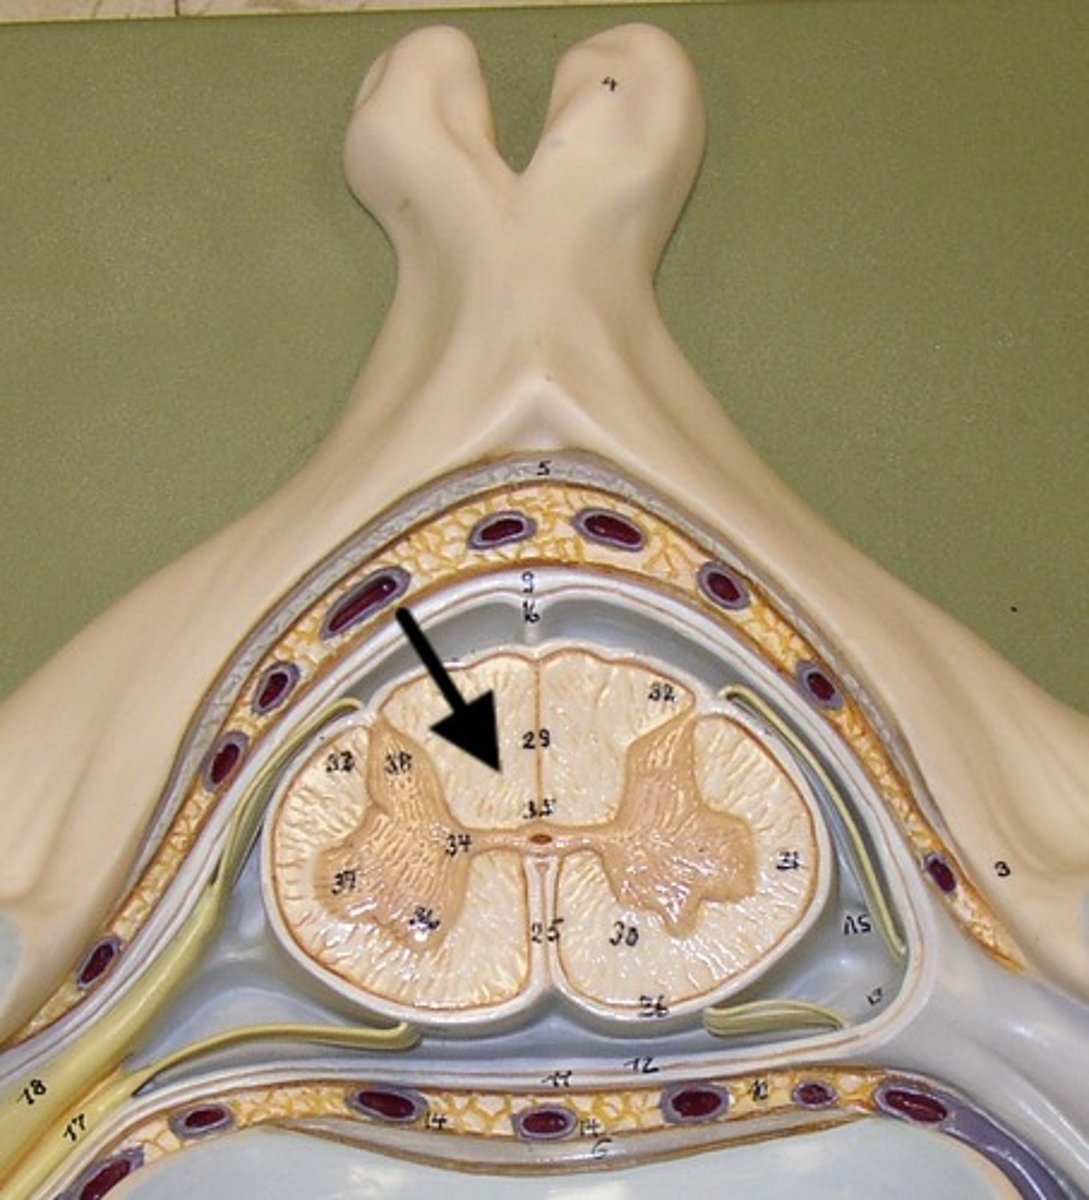

white matter of spinal cord

Primarily myelinated axons, but also has unmyelinated axons

Contains major sensory and motor tracts to and from the brain

gray matter of spinal cord

Mostly neuron cell bodies, neuroglia, unmyelinated axons

Has central canal in the middle - contains cerebrospinal fluid

Site for integration of postsynaptic potentials

posterior gray horn

A

Location of sensory nuclei

lateral gray horn

B

Contains Motor nuclei (visceral)

only in thoracic and lumbar vertebrae

anterior gray horn

C

Contains Motor nuclei (Somatic)

posterior white column

Sends information up to the brain

sensory info

lateral white column

Information descends from the brain

anterior white column

Information descends from the brain (Brings info back to the spinal cord)

motor commands

central canal of spinal cord

contains cerebrospinal fluid

posterior median sulcus

anterior median fissure